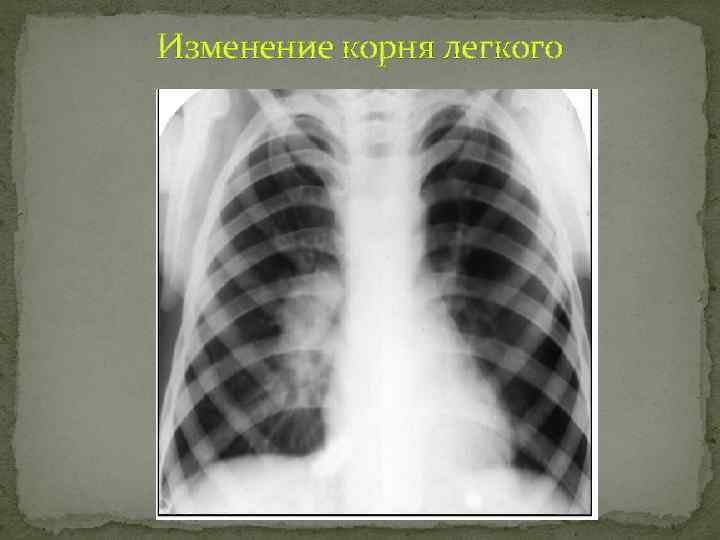

Изменение корневого рисунка Синдром изменения корней легких проявляется изменением их величины и формы, ухудшением структурности изображения, неровностью и нечеткостью контуров. Инфильтрация клетчатки корня Увеличение лимфатических узлов Деформация корня фиброзная Для установления характера патологического процесса наряду с особенностями скиалогической картины нужно учитывать, являются ли эти изменения одно или двусторонними.

Изменение корня легкого